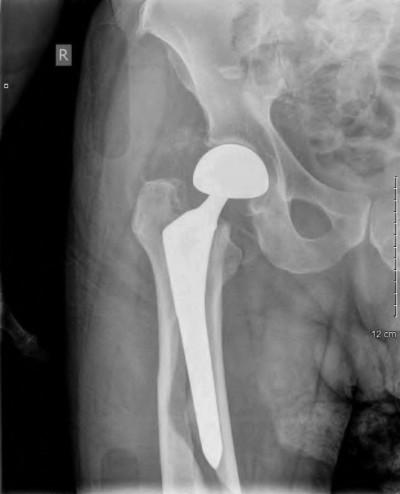

A 72-year-old male presents 2 years status post fixation of an impending pathologic right femur fracture due to metastatic renal cell carcinoma. He is minimally ambulatory due to pain. Despite radiation therapy, there has been progression of the lesion with extensive cortical bone loss, which is shown in Figure A. A proximal femoral replacement arthroplasty is performed without complications, and is demonstrated in Figure B. Which of the following is true regarding this patients post-operative course?

Deep prosthetic infection is the most common complication after hip arthroplasty performed for salvage of failed internal fixation after pathologic proximal femoral fracture secondary to malignancy.

Jacofsky et al reviewed the complications in 42 patients with a mean age of 63 who were treated with hip arthroplasty for salvage of failed treatment of a pathologic proximal femoral fracture. Multiple different constructs were used.

The most common complication was deep prosthetic infection, which occurred in nearly 10% of the patients studied. All infections occured in patients whom had previously received radiation. The mean Harris Hip score improved from 42 to 83 points post-operatively, and 41 of the 42 patients were ambulatory at follow-up. Implant survivorship free of revision for any reason at 5 years was 90%, and free of revision for aseptic failure or radiographic failure was 97%.

Figure A shows a lytic lesion of the proximal femur with an intramedullary implant. Figure B shows a proximal femoral replacement.